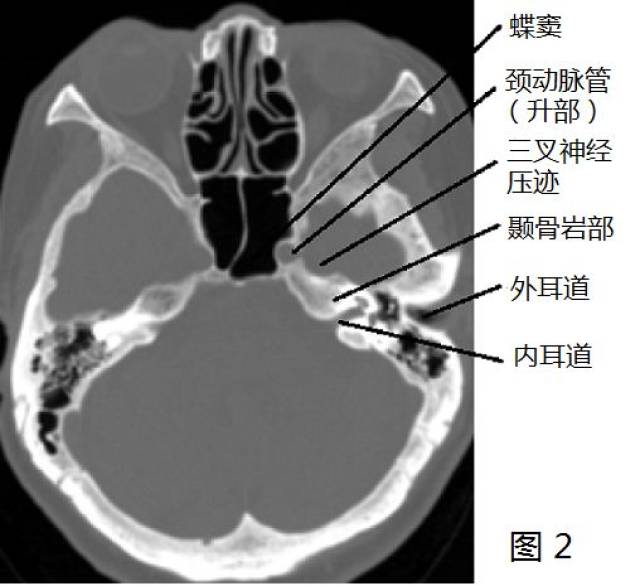

颈内动脉走形图谱(2):岩段和破裂孔段

640x431 - 34KB - JPEG

551x560 - 33KB - JPEG

508x465 - 29KB - JPEG